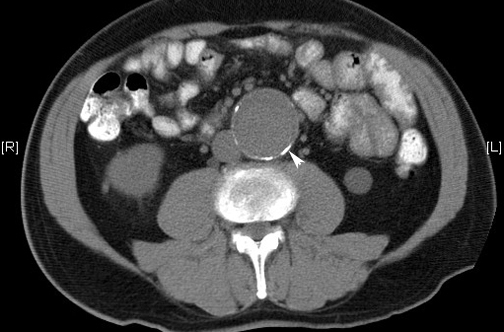

Aten Primaria, enero de 2019 La ecografía en atención primaria realizada por médicos de familia tras una formación básica para detección de de aneurisma de aorta abdominal (AAA) muestra muy alta validez diagnóstica. Habría que valorar con estudios más amplios de efectividad la pertinencia de implantar un sistema de detección precoz de AAA en población de riesgo.

Hay un descenso de la incidencia de mortalidad en las últimas décadas que excede a los efectos del rastreo, y que vuelve menos claro el balance de los riesgos y los beneficios del cribado. The Lancet, 14 de junio de 2018

En un ensayo clínico realizado en Dinamarca se muestra el beneficio de rastrear en los varones de 65 a 74 años la presencia de aneurisma de aorta abdominal, enfermedad arterial periférica e hipertensión. The Lancet 28 de agosto de 2017